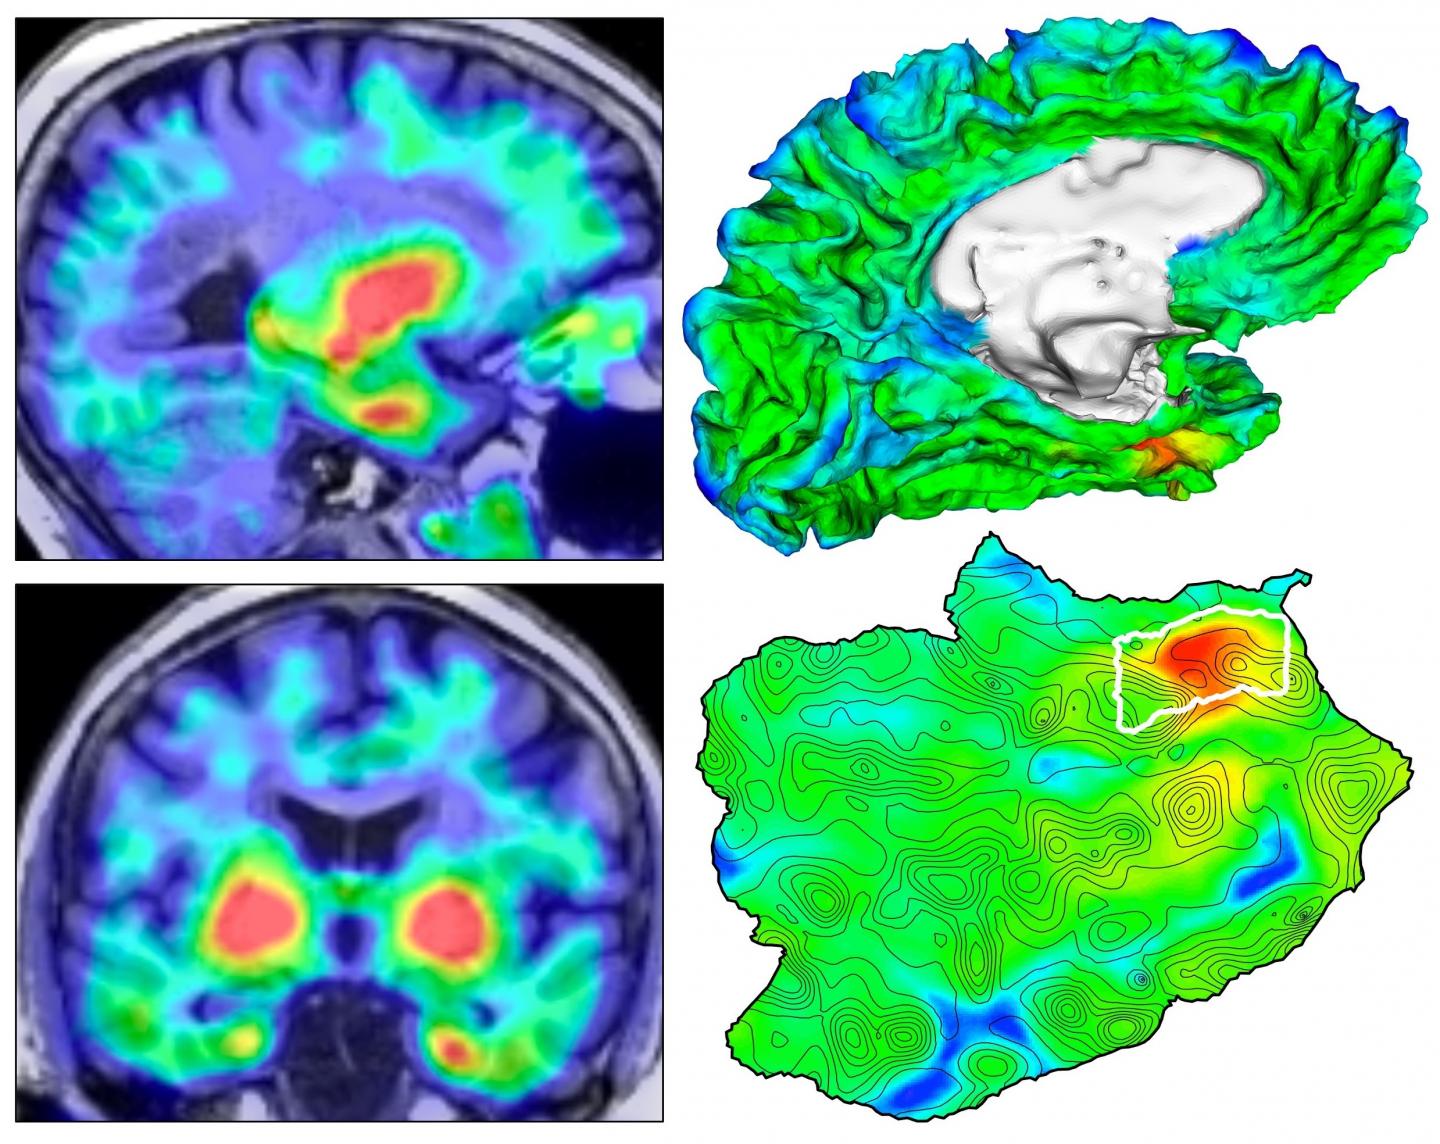

PET scans show activity of the brain network that is linked to changes in connectedness.